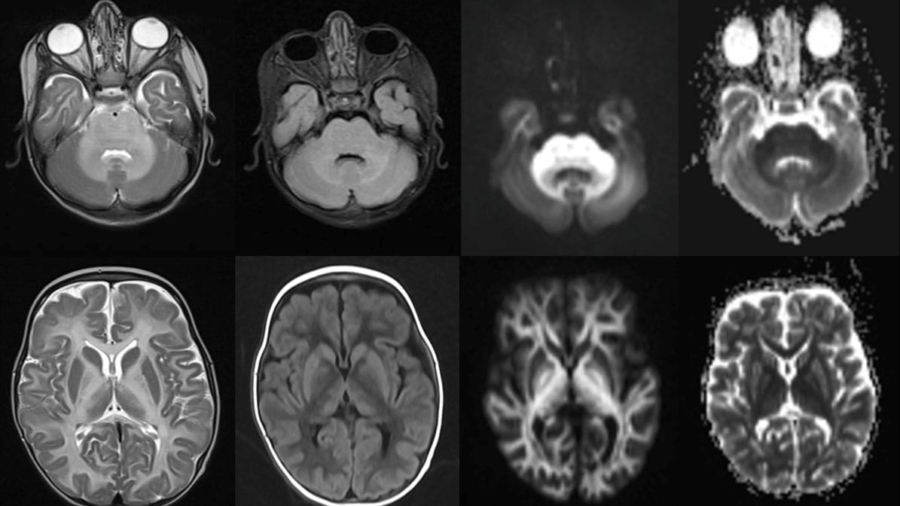

9-year-old female with URI for 1 week, fever for 3 days, seizures and altered sensorium for 1 day.

November 2025